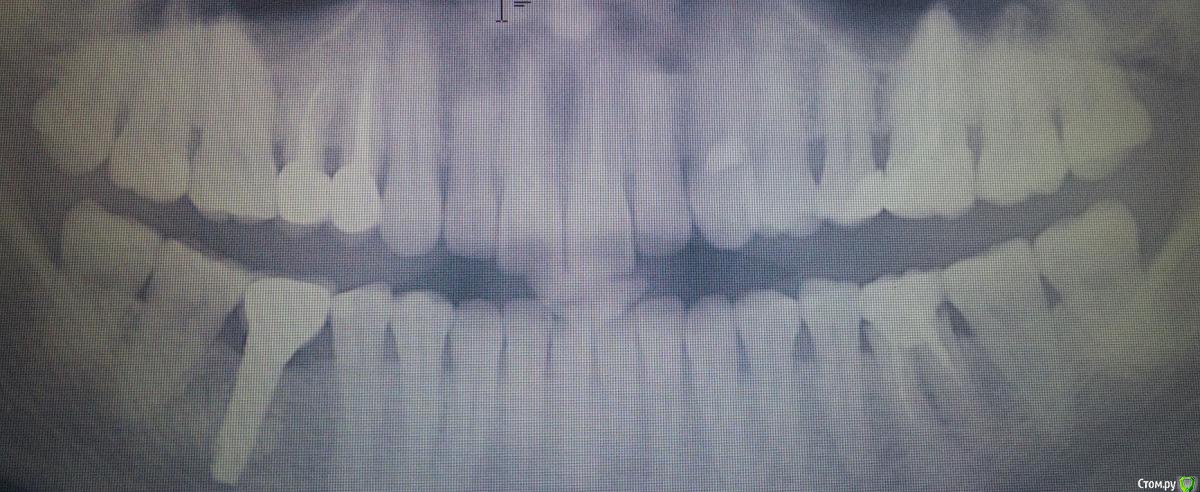

Kast Опубликовано 5 января, 2017 Поделиться Опубликовано 5 января, 2017 (изменено) Здравствуйте, уважаемые доктора! 24.12.16 я в плановом порядке удалила нижний 6-й резорциновый зуб. Прикрепленный панорамный снимок - до удаления. Зуб пришлось выламывать вместе с куском челюсти, затем хирург добавил в лунку 250мг материала био-осс коллаген и закрыл все это мембраной российского производства. Мембраны не хватало, поэтому хирург разрезал ее напополам и сшил так, что шов проходил ровно посередине лунки. 5 дней после удаления все было хорошо, пила антибиотики, мазала лунку солкосерилом, делала ванночки с хлоргексидином, на осмотр 28 декабря я не смогла прийти, но не волновалась, потому что зуб уже совсем не беспокоил. Но еще через два дня лунка начала болеть, и внутри, десна вокруг, 30го и 31го пришлось принимать обезболивание. Клиника и хирург ушли на каникулы, связаться не было возможности. 1го появилась температура 37,5 и держалась 3 дня, 2-го лунка и десна перестали болеть, периодически во рту появлялись кусочки костного материала, момент, когда разошелся шов посреди мембраны, я не отследила. 4-го показалась на приеме у хирурга, он снял швы и убрал сверху мембрану, сказал показаться через месяц. Лунка сейчас вот в таком состоянии, прицельный снимок сделан 2-го января, костный материал продолжает большими кусками отваливаться из лунки, я боюсь, что он весь вывалится и я буду ходить с открытой костью. Врач обещал, что за 100 тысяч удалит зуб и одномоментно поставит имплант, после операции выяснилось, что имплант поставить не получилось, счет только за удаление и биоматериал с мембраной составил 80 тысяч. Мембраны уже нет, биоматериала почти тоже, а теперь по результату за эти деньги у меня только огромная дыра Подскажите, пожалуйста, что-нибудь сейчас можно сделать, чтобы как-то поправить ситуацию? Или остается только ходить с дырой и ждать, пока она сама заживет?Несет ли клиника какую-либо ответственность в таких случаях? Второй день плачу, зачем я полезла удалять этот зуб, который не беспокоил больше 15 лет, только выглядел не эстетично Изменено 5 января, 2017 пользователем Kast Ссылка на комментарий

gum Опубликовано 5 января, 2017 Поделиться Опубликовано 5 января, 2017 Я бы убрал все из лунки, кюретаж, и провел бы все под 《сгустком крови》, через 3 месяца 3Д снимок и принятие решения о имплантации. К сожалению ситуации разные бывают, по ОПТГ высота кости хорошая, так что думаю все у вас будет хорошо Ссылка на комментарий

колесников Опубликовано 6 января, 2017 Поделиться Опубликовано 6 января, 2017 Здравствуйте! Во первых сочувствую Вам. К сожалению это только начало длительной эпопеи заживления. Лунка инфицировала и теперь там альвеолит. Доктора не стоит винить,зуб был не подарок. На снимке видео что верхушки у него имели бутылочное расширение и периодонтальная щель не прослеживалась,все это говорит о технических сложностях при удалении. Доктор должен довести лунку до полного заживления,будьте с ним в контакте,не пропускайте визиты. Рекомендовал бы содовые ванночки дома или слабый марганцевый Р-ор,приём антибиотика ципралет -а или трихопола,аппликации метроном-Дента. Эти рекомендации лучше обсудить с Вашим лечащим врачом. Ссылка на комментарий